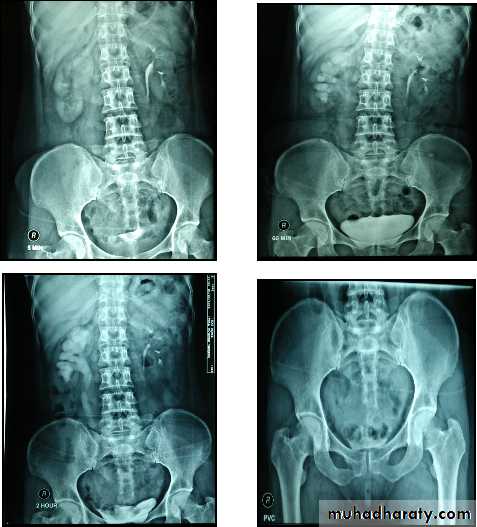

Intravenous Pyelogram (IVU)

The IVU series consist of:1-KUB film…To identify any calcification like stones or nephrocalcinosis.

2-Post contrast film…

The post contrast series:

IV access is required for administration of the contrast material.The contrast dose is usually instilled at a fast (bolus) rate.

The calyces are usually not visualised in <2 minutes following contrast administration - This is the NEPHROGRAM phase.

Serial images are taken at 5-20 minutes for visualisation of the PCS and ureters…This is the PYELOGRAM or EXCRETORY phase.

Lastly take a full bladder and a post-void film.